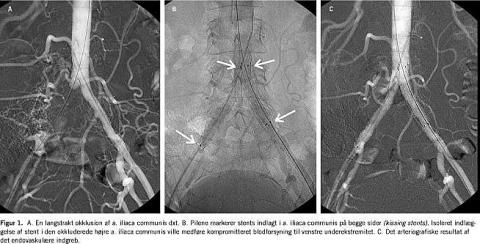

Endovaskulær kateterbaseret behandling er ofte mulig at foretage og er selvsagt mindre belastende for patienten end et kirurgisk indgreb. Patienter, der for nylig har haft trombose eller emboli, kan i nogle tilfælde behandles med trombolytika, som infunderes intraaterielt over timer evt. gennem flere døgn. Tilfredsstillende trombolyse kan gennemføres selv flere uger efter akut opstået iskæmi, men resultaterne er bedst ved hurtig behandling [1]. Endovaskulær behandling udgøres hyppigst af perkutan transluminal angioplastik (PTA). PTA er en ballonudvidelse af det obstruerede kar. Samtidig indlægges ofte en stent, et tyndt rørformet metaltrådsgitter (Figur 1 ). Stents fremstilles kommercielt i mange former og størrelser og i forskellige typer af metallegering. Stenten indføres komprimeret gennem katetret, ekspanderes ud for stenosen og klemmes fast på væggen. Stentens formål er at opretholde det oprindelige lumen, og det har vist sig, at stents både øger den primære succesrate og i mange tilfælde også det langsigtede resultat af PTA [2-5]. Især i mindre kar kan der imidlertid opstå restenose, når karvægshyperplasi vokser gennem metalgitteret. For at modvirke restenose er nogle stents præparerede med celleproliferationshæmmende lægemidler, og de hidtidige undersøgelser af disse drug eluting stents har vist meget lovende resultater. Visse stents, som har påmonteret protesemateriale, kan endvidere benyttes til behandling af aneurismer eller til lukning af karlæsioner.